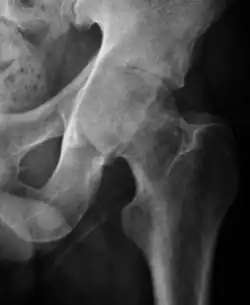

Slipped capital femoral epiphyses (SCFE)

Slipped capital femoral epiphyses (SCFE) usually affect 11- to 14-year-old adolescents (Figure 4). Radiographs may show widening and irregularity of the physis and posterior inferior displacement of the capital femoral epiphysis. On the AP view Klein’s line, tangent to the lateral aspect of the femoral neck, does not intersect the femoral head indicating that it is displaced. SCFE may compromise the blood supply to the femoral head and cause avascular necrosis, mainly when there is instability between the fragments.[1]